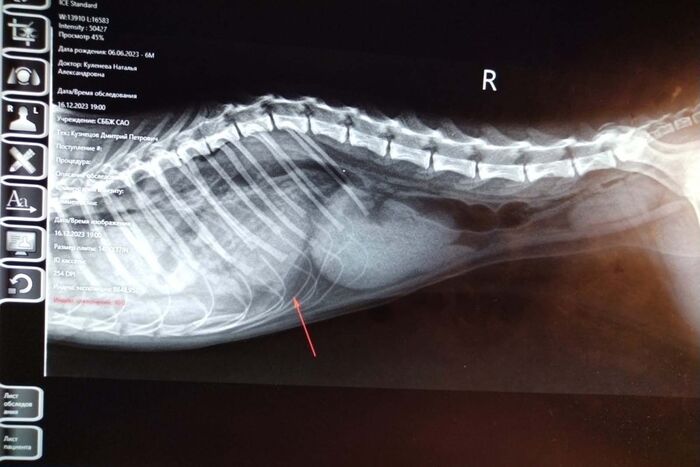

А бенгальская кошка Анабель пострадала еще серьезнее: во время игр она упала со шкафа. Рентген показал диафрагмальную грыжу и смещение органов в грудную полость. Хирург Роман Тимофеев прооперировал питомца под ингаляционным наркозом с использованием искусственной вентиляции легких. Оба пациента сейчас восстанавливаются, их здоровье вне опасности.